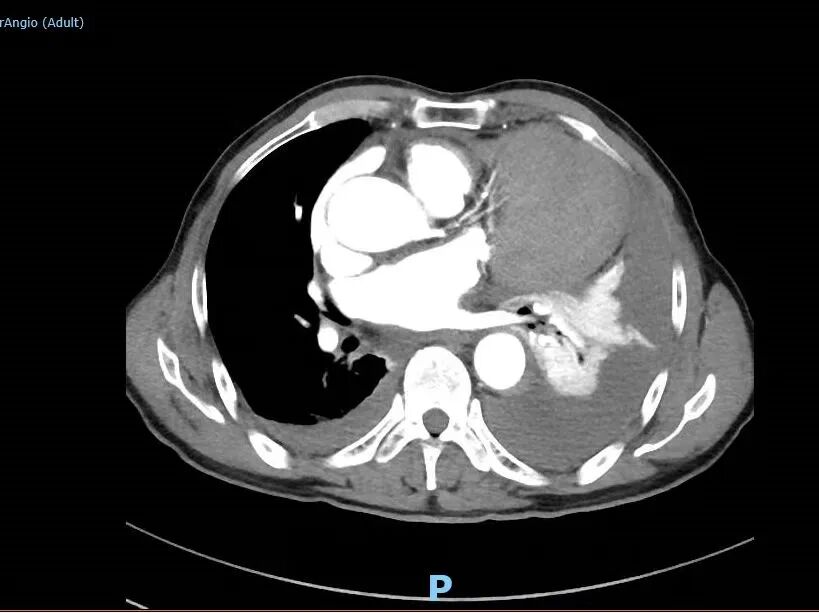

不慎扭腰 疼痛威胁老人生命 据患者的大儿子曹先生介绍,老人今年75岁,家住旺苍县盐河镇,病前一直在家务农。 5月22日晚上20时许,老人洗漱结束后,在院坝里向外泼脏水时,感觉“闪”了一下腰,腰间传来阵阵刺痛。 不一会儿,疼痛加剧,老人有点受不住了。 居家的大媳妇通过电话把情况告诉了在外务工的丈夫曹先生。曹先生认为老人是扭伤了腰,到村卫生室处理一下,拿点止痛药吃就可以了。 大约当天晚上21点多,老人到村卫生室输上了液,结果症状未缓解,痛得汗珠如豆而下。 什么原因导致仅仅是闪了一下腰的老人,突然胸背部产生如此剧烈的疼痛呢? 在没有任何检测硬件条件支撑的村卫生室,病因难以诊断。 在剧烈疼痛持续到第二天早上时,大家提议将其送往县城医院检查。 5月23日上午9时,家人协调到一个亲戚的轿车,将老人送往县城医院。同时,老人在外务工的2个儿子也启程往家乡奔赶。 检查结果显示。主动脉夹层壁间发现血肿,初步诊断为主动脉夹层动脉瘤,考虑患者病情复杂、危重,随时有生命危险,该院医生建议将老人转至广元市第一人民医院就诊治疗。 联合会诊 精准把脉制定大胆“计划” 经过30个小时的辗转,5月24日凌晨2点12分,老人入住广元市第一人民医院,结束了颠簸煎熬。 医院连夜安排了一系列的复查复诊。 然而结果扑朔迷离…… 老人除了疼痛一直没有缓减外,还伴有胸闷、气紧、体表汗流不止等情况,体力受限、但没有明显的活动障碍,没有意识丧失、呕血、黑便、大小便失禁等现象。加上CTA检查主动脉夹层壁间血肿现象明显,综合结果显示,基本和旺苍县县城某医院初诊特征一致。 术前,CTA影像显示,患者左前纵隔巨大占位和左胸腔大面积积液。 但是,问题来了。 老人前纵隔显现大面积阴影,可以确诊为合并前纵隔占位,这一占位是恶性肿瘤还是良性肿瘤,还是其它原因? 前纵隔占位的性质,直接威胁到老人的生命安全,也是治疗方案的关键点。 同时,老人左胸腔伴随着大量积液,积液之多已经把左肺压迫得只有一个成人手拳头大小,这一特征又有点像血管破裂导致。 如果是血管破裂导致,老人因失血过多而发生猝死的风险几率非常高! 那么,胸腔积液到底是什么?它是前纵隔占位诱因还是因血管破裂引起的呢? 5月24日早上,广元市第一人民医院副院长、心胸外科专家何东权在例行巡房时,了解到老人病情的特殊性和复杂性,当即表示:首先确定胸腔积液的成分,来推断老人的病情症结所在。 “看到一针管鲜红的液体,我紧绷的心弦稍稍松了点。”心胸血管外科医师王贤芝通过穿刺取样看到积液颜色,基本断定为血液,而且是鲜血。随后,分析数据也显示积液以血液成分为主体。 即使胸腔积液是血液,也不排除是前纵隔占位引起的出血。 医院又对老人进行主动脉三维重建,显示主动脉弓大弯侧外壁有明显的凸起点,疑似破裂出血灶。 这一结论让老人的主管医生薛春竹忧喜参半:“主动脉夹层破裂导致大量血液漏浸形成胸腔积液的可能性相对较大,反之前纵隔占位引起积液的可能性减少,虽然它对老人的生命依然存在不容忽视的威胁,但相对乐观了不少”。 各类检查结果汇总后,何东权副院长召集心胸血管外科和影像科等相关科室专家进行了联合会诊,大家纷纷发表意见,就疑点进行多角度分析。 讨论的焦点还是集中在前纵隔占位的形成因素以及与胸腔积液的关系。 “前纵隔占位若是恶性肿瘤,那么手术治疗毫无意义。” 老人的病理特征有诸多不合常理的地方,“如果左胸腔内全是血液,为什么患者在大失血前提下,还没有休克?” CT室专家认为,从影像看,前纵隔占位虽然有肿瘤特征,但阴影部分密度分散,而且前纵隔和胸腔之间有清晰的隔离带,不排除因胸腔积血通过膜壁薄弱处渗透到前纵隔而形成占位阴影的可能。 “患者病情恰恰特殊在于,左胸腔积液把左肺压迫收缩到只有拳头大小,也就把左肺中的肺循环体系内约500ml血液挤压进入人体血液大循环中,补充了体供血液量,这或许是目前患者没有休克的主要因素。”心胸血管外科主任医师张文林分析。 “如果前纵隔占位是肿瘤,唯一的办法是开胸手术。高龄、大失血,加上伴有肾功能、前列腺增生等其它病情,老人基本上坚持不到开胸手术结束。”心胸血管外科医师何杨提出自己的担忧。 “老人家的血还在漏失,随时可能发生猝死,十分危急。”何东权副院长提议,根据老人的“突然疼痛、胸腔积血”等病理特点,利用微创技术,只针对出血点进行修复性抢救治疗,目前,保生命是最大的前提。 这一提议得到大家一致认可。 30分钟 上演生命抢夺战 5月26日早上8点,手术开始。 手术施展开来就是和时间赛跑,和死神赛跑。 麻醉之后,从足背动脉穿刺右侧股动脉一路上行,边走边造影,行至升主动脉后,造影显示,主动脉弓大弯侧外壁破口明确,和术前主动脉三维重建显影吻合。 医生沿左锁骨下动脉后缘远端释放支架覆盖主动脉弓大弯侧外壁,覆盖后,造影显示,血管显影良好,未见明显内漏。 短短30分钟,在先进硬件设施设备的帮助下,广元市第一人民医院心胸外科的专家们,凭借精诚团结的团队精神、默契配合和高超技艺,成功堵住了老人体内血液循环体系的“决堤口”,将老人的生命从死亡的边缘上“拉”了回来。 术后,一边输血,一边从老人左胸腔抽出1000ml多的积血。 目前,老人左肺恢复正常,精神面貌、饮食状况得到有效改善,胸背部疼痛消失,身体机能全部转优。 术后,患者左前纵隔占位逐渐减小 左胸腔未见积液 术后,患者主动脉弓大弯侧外壁光滑 未见内漏 术后第三天,患者各项指标转优